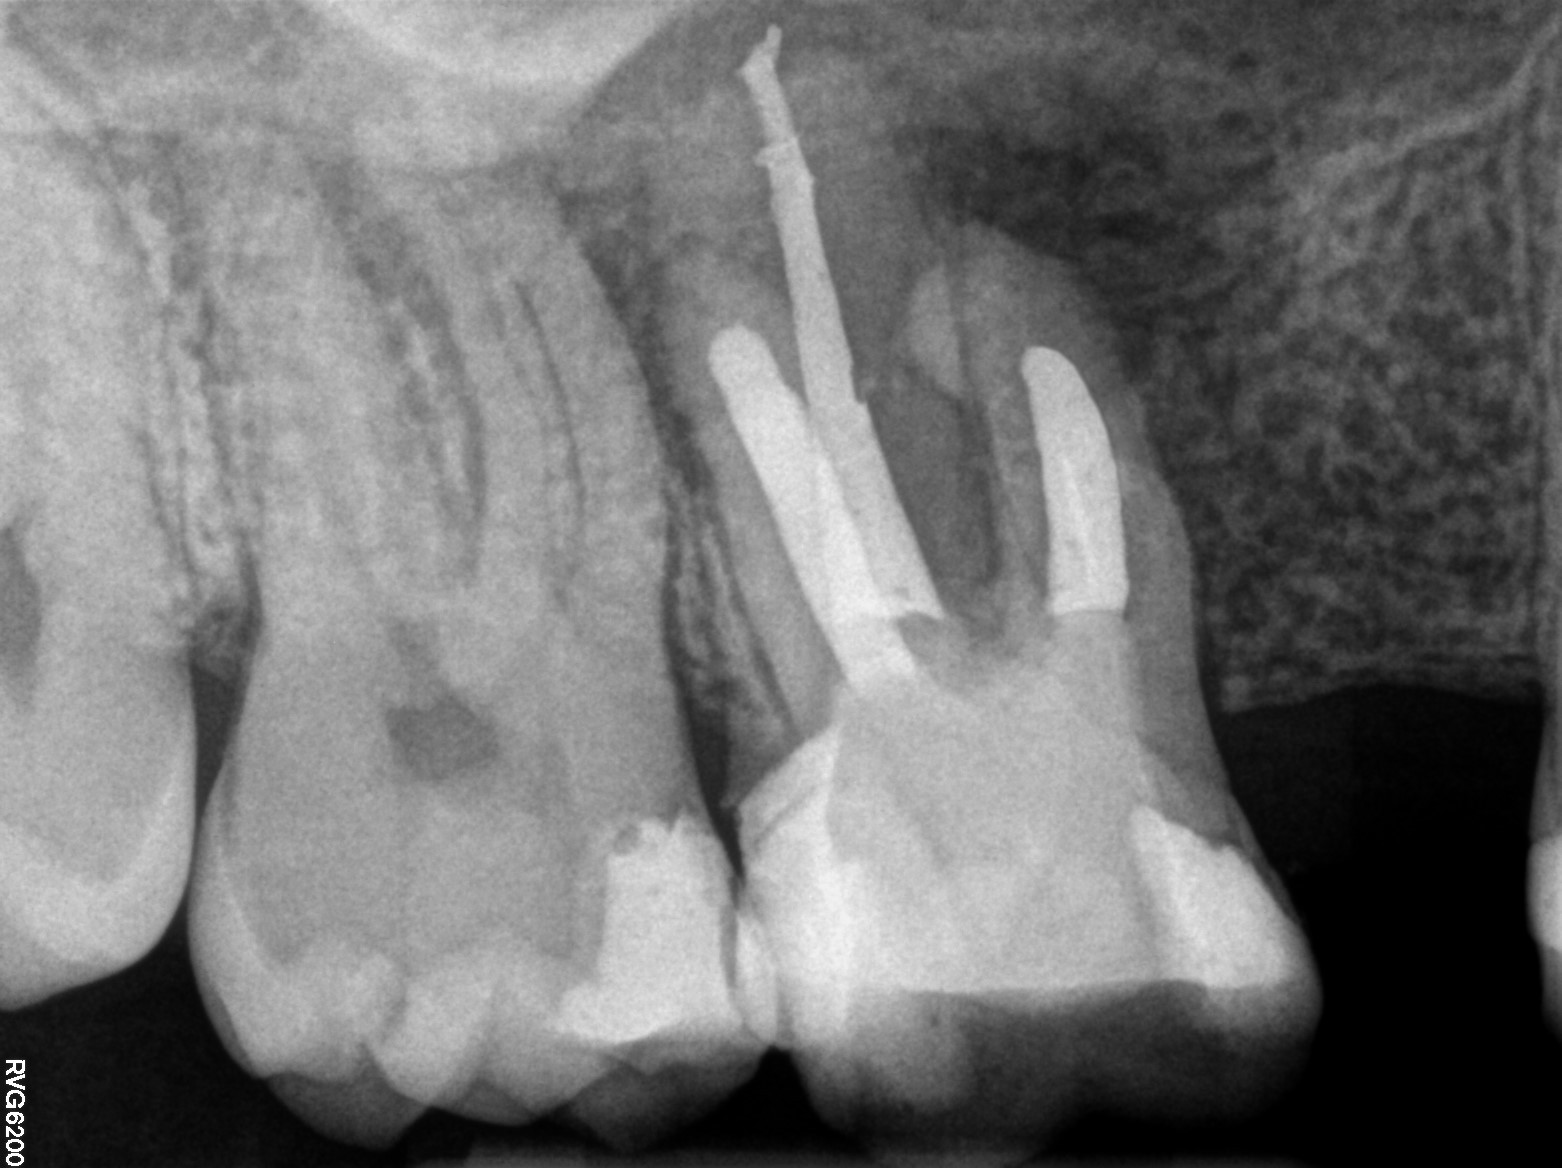

Kanały policzkowe udało się opracować i wypełnić do 1/3 wierzchołkowej, dalsze części kanałów były całkowicie zobliterowane. W trakcie opracowywania kanału podniebiennego zauważono wyciek żółtego opalizującego płynu spoza wierzchołka korzenia zęba, który po kilku minutach samoistnie ustał. Zasugerowało to obecność torbieli korzeniowej. Po zakończeniu leczenia endodontycznego wykonano zdjęcie punktowe kontrole (ryc. 2) oraz tomografię komputerową wiązki stożkowej (cone beam computed tomography – CBCT) opisywanego zęba. Jej rezultat przedstawiają ryciny 3‑6. Widzimy na nich znacznych rozmiarów torbiel korzeniową, która w toku leczenia musi zostać usunięta. Ustalono rozpoznanie ostateczne – torbiel okołowierzchołkowa. Omówiono z pacjentem jego stan i zaproponowano dalsze leczenie, na które wyraził zgodę.

Ryc. 2. Zdjęcie zęba 16 po leczeniu wykonane w systemie radiografii cyfrowej.